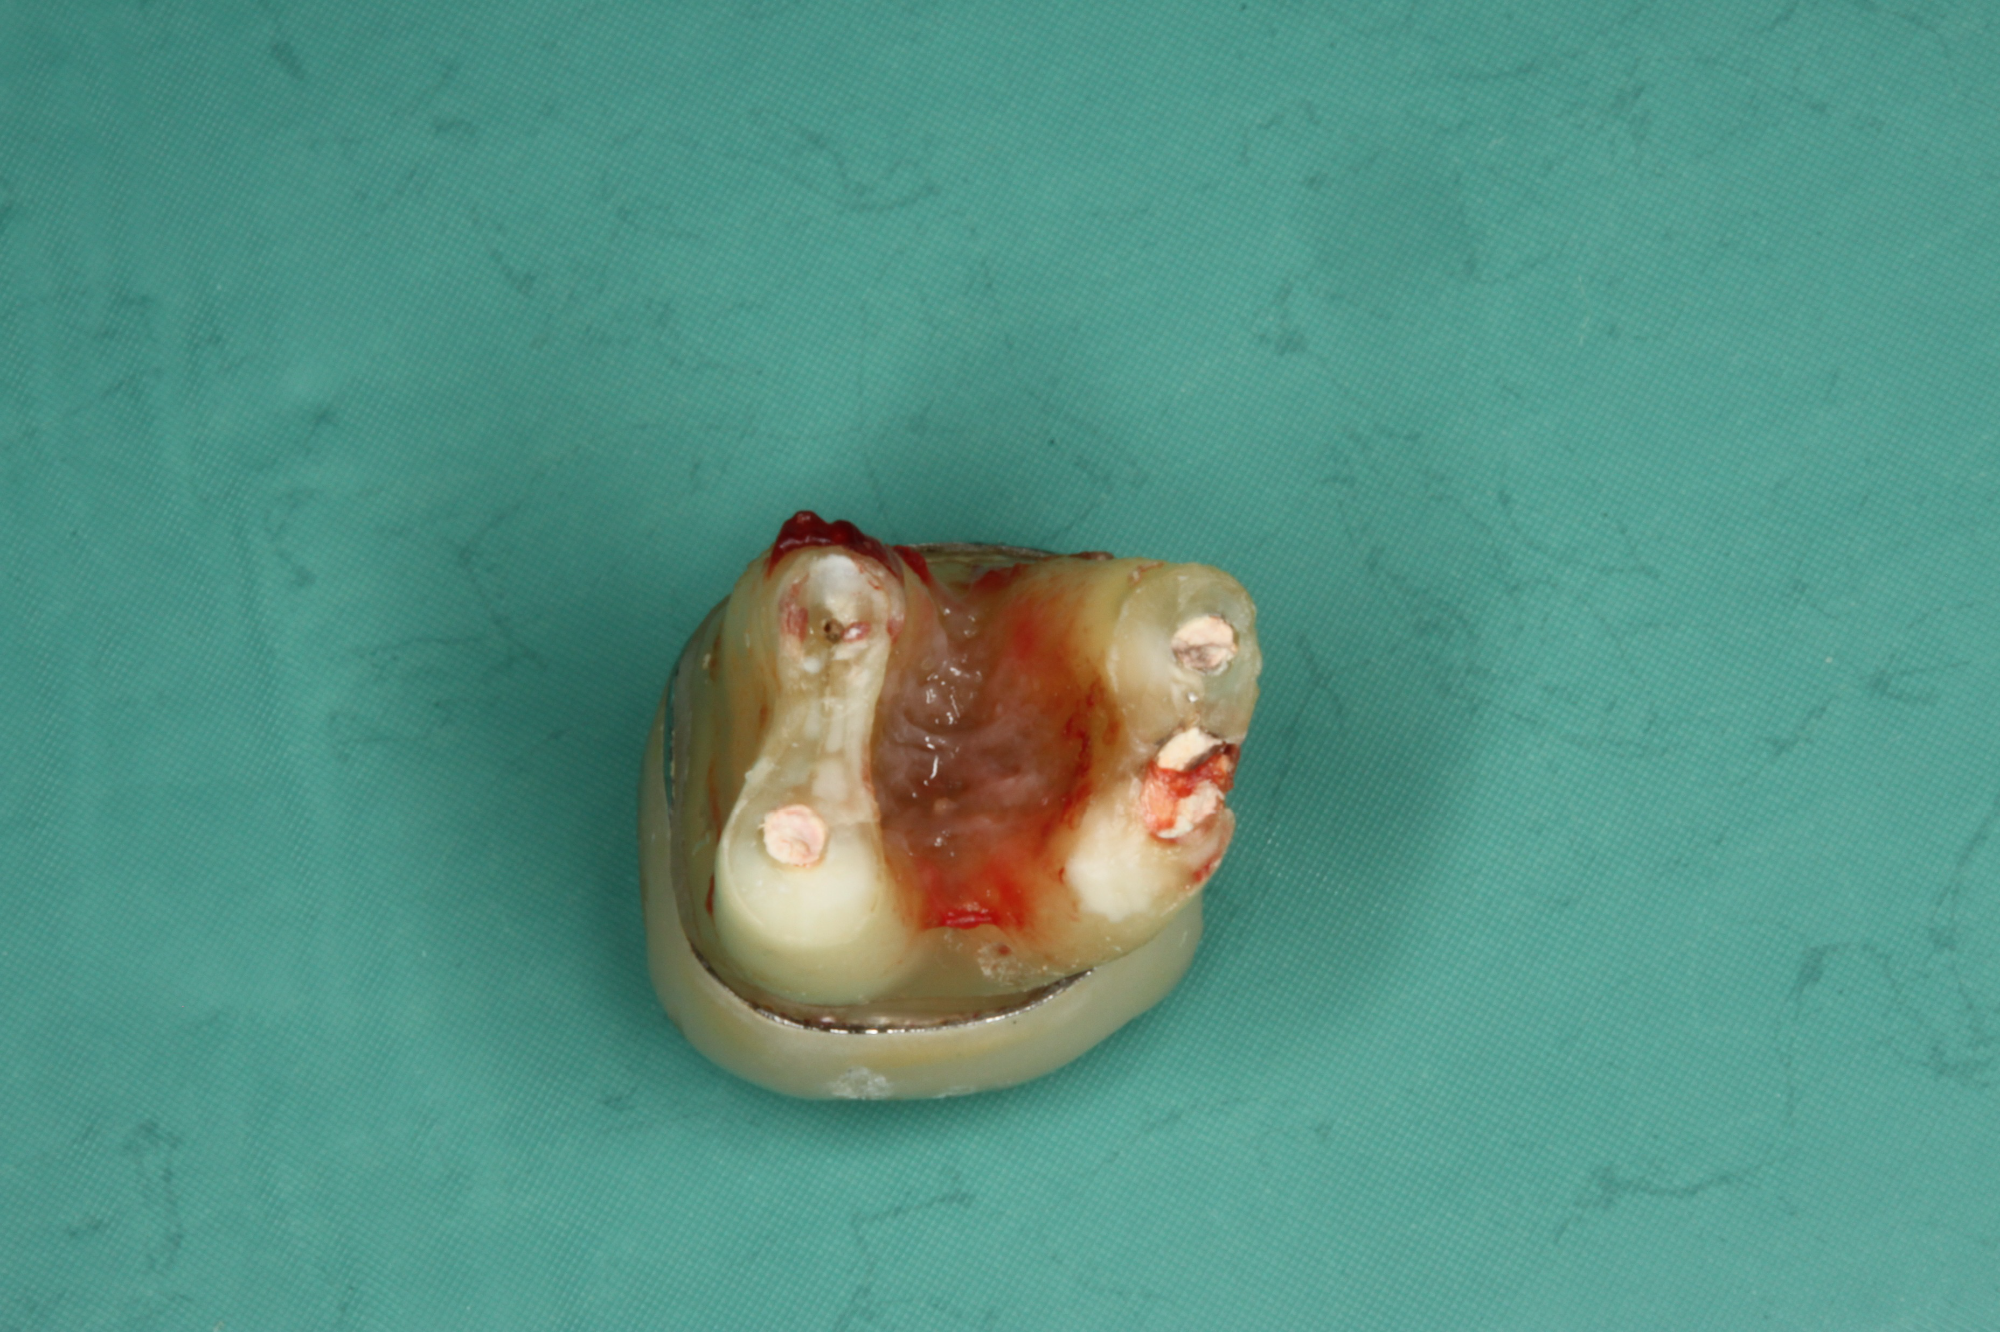

Wurzelkanalbehandelte Zähne sind tote Zähne! Auch die beste Mikro-Endodontie wird kaum eine komplett bakteriendicht abgeschlossene Wurzel realisieren können. Akzessorische Seitenkanäle und die Endo-Paro Verbindung über die Dentintubuli bleiben bestehen.

Pro Quadratmillimeter Wurzeldentin befinden sich 40 bis 60 tausend Dentinkanälchen, welche sich dann auf eine Länge von etwa 1 – 5 km summieren.

Dentinkanälchen sind 1 – 3 μm weit. Erreger (Bakterien, Pilze, Viren) haben eine Größe von 0,6 – 1 μm.

Makrophagen haben eine Größe von 5 – 20 μm.

Die Entfernung wurzelkanalbehandelter Zähne in unserer Praxis

Der Austausch wurzelbehandelter und toter Zähne erfolgt so schonend wie möglich. An die Stelle des toten bzw. wurzelbehandelten Zahnes wird direkt in derselben Behandlung ein Keramikimplantat gesetzt, wenn genug gesunder Knochen vorhanden ist.